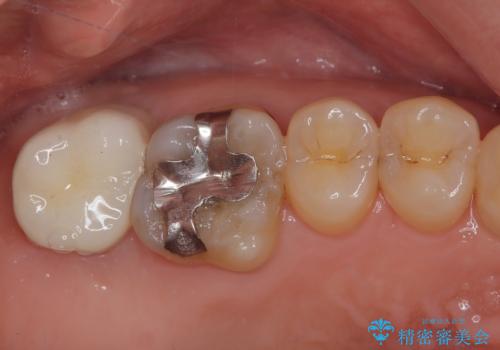

上顎の奥歯は、左右ともに外側に転位しており、特に右上はむし歯の範囲が広く、根管治療も必要な状態でした。

上顎左右の歯をアンカースクリューを用いた部分矯正により位置を修正し、オールセラミッククラウンにて補綴治療を行うこととしました。

矯正治療に時間はかかりましたが、外側に飛び出した歯が内側に収まったことで、非常に歯が磨きやすくなったとのことでした。